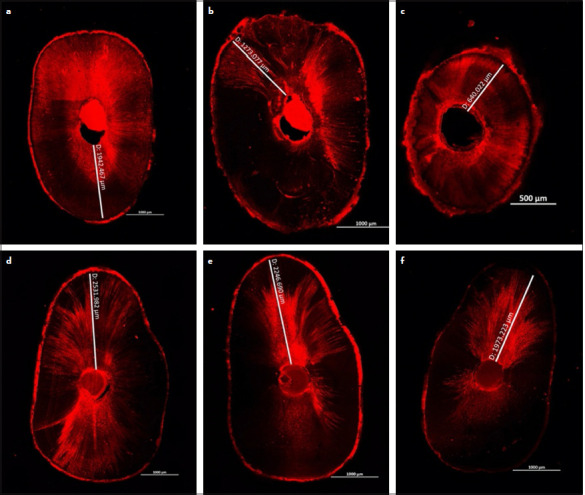

Methods: Eighteen extracted single-rooted mandibular premolars were randomly divided into two groups (n=9) according to the obturation technique used. The maximum penetration depth in microns, percentage of penetration depth, and percentage of penetration area of the NeoSEALER Flo bioceramic sealer were assessed using confocal laser scanning microscopy at different root levels; coronal, middle, and apical. Data was statistically analyzed using Kruskal-Wallis's test followed by Dunn's post hoc test with Bonferroni correction and Friedman's test followed by Nemenyi post hoc test with the significance level set at p<0.05.

Results: The single cone obturation technique has shown a statistically significantly higher percentage area of NeoSEALER Flo penetration than the lateral compaction technique at the coronal root level only. Otherwise, both obturation techniques have shown no statistically significant differences in NeoSEALER Flo penetration distance, percentage of penetration distance, and percentage of area penetration at the middle and apical root levels.